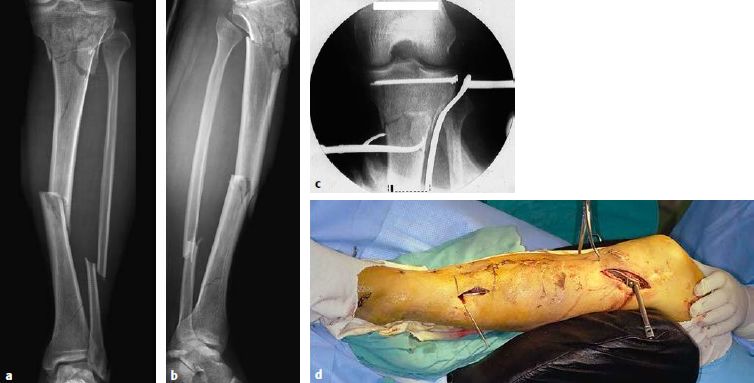

图片图6.8.1-23 a-e 后侧柱骨折

一名43岁男性骑摩托时受伤,他的左腿发生了胫骨平台的后侧柱骨折

a  术前X线;b  CT横断位显示内侧骨块累及了后侧柱,同时后侧中央存在关节面的塌陷;c  对这名患者使用倒L入路;d  一块4.5mm长钢板放置在柱上,T型钢板被用来支撑关节面的塌陷;e  术后X线